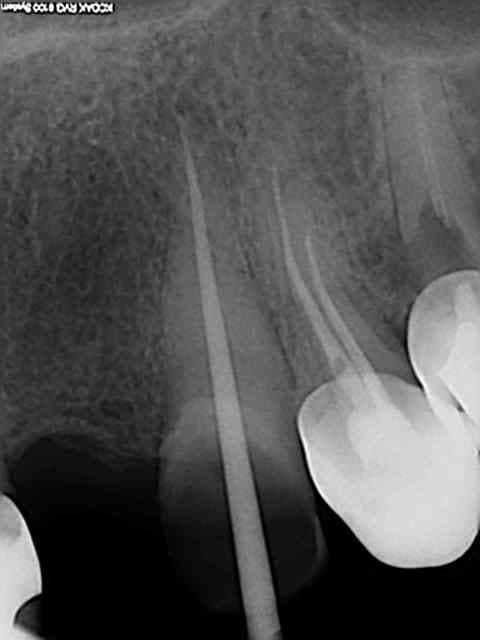

J'ai reposté quelques radios de biopulpectomies

RTE dans un précédent post...